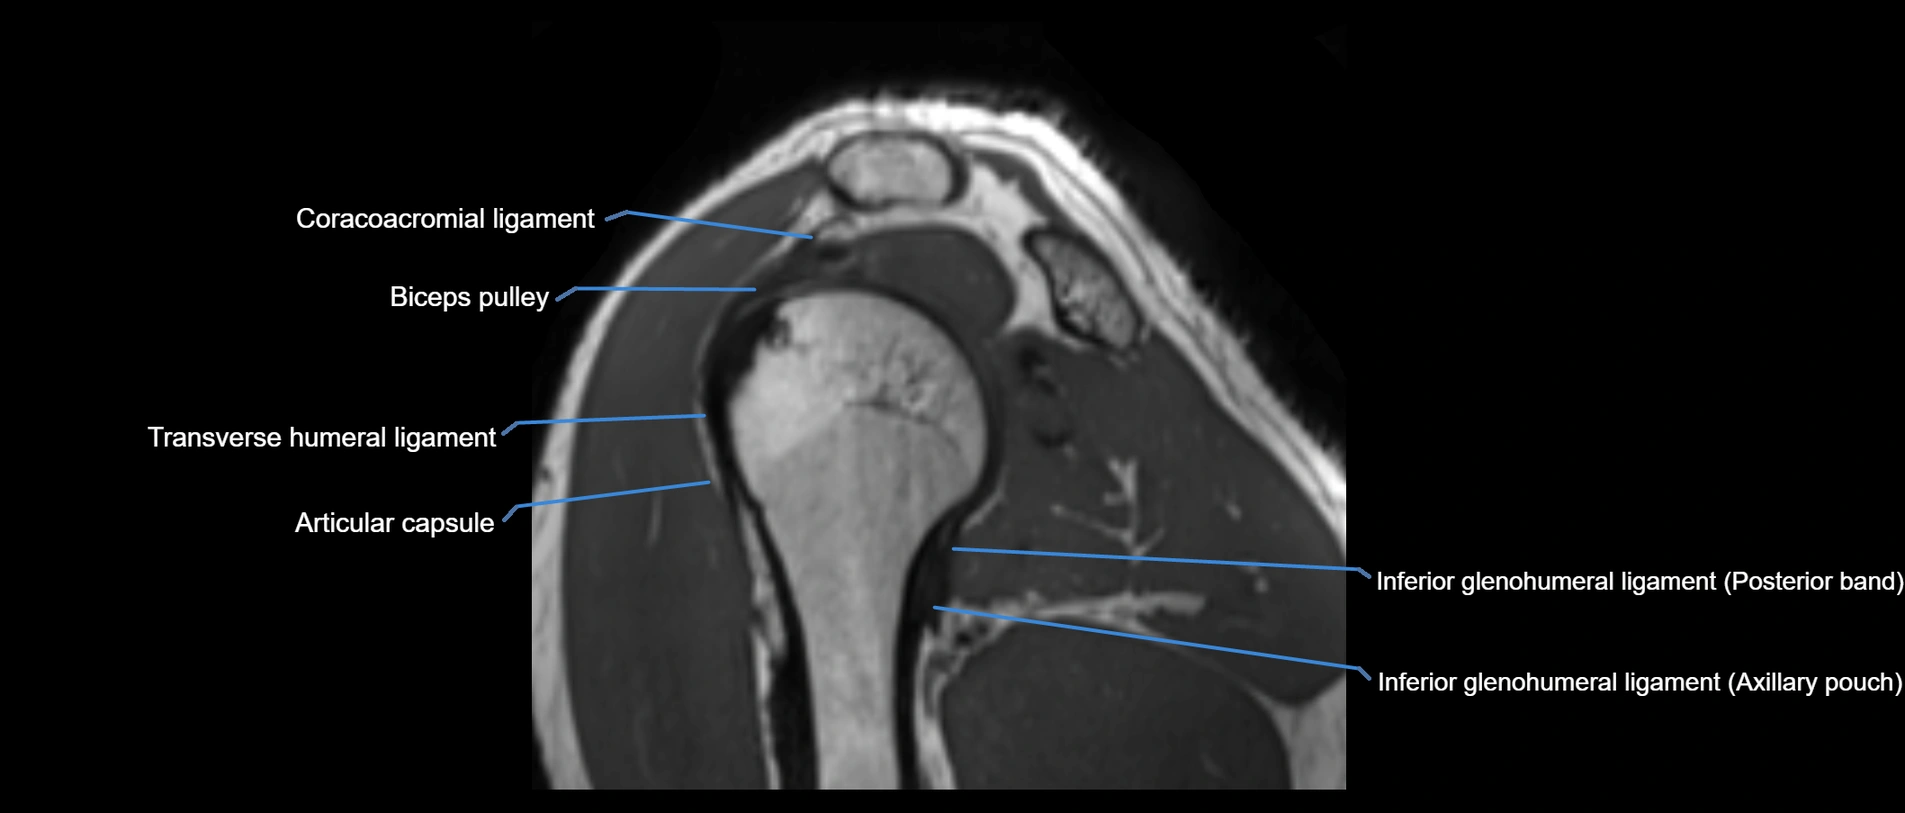

MRI images

image